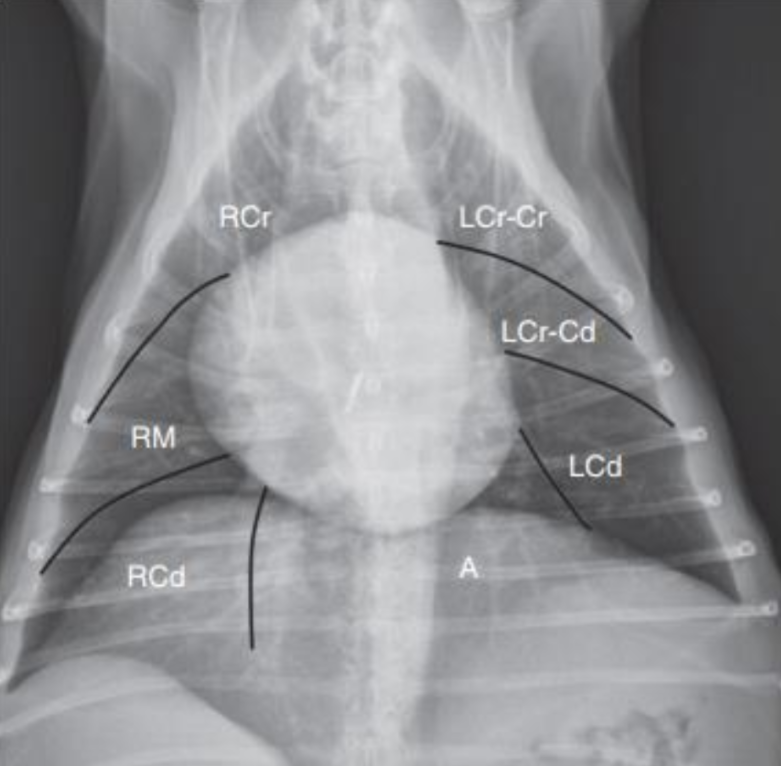

• 우 4엽, 좌 2엽으로 총 6엽이다.

• 외측상은 겹쳐 보여 선호되지 않고, DV나 VD - 특히 VD가 선호된다.